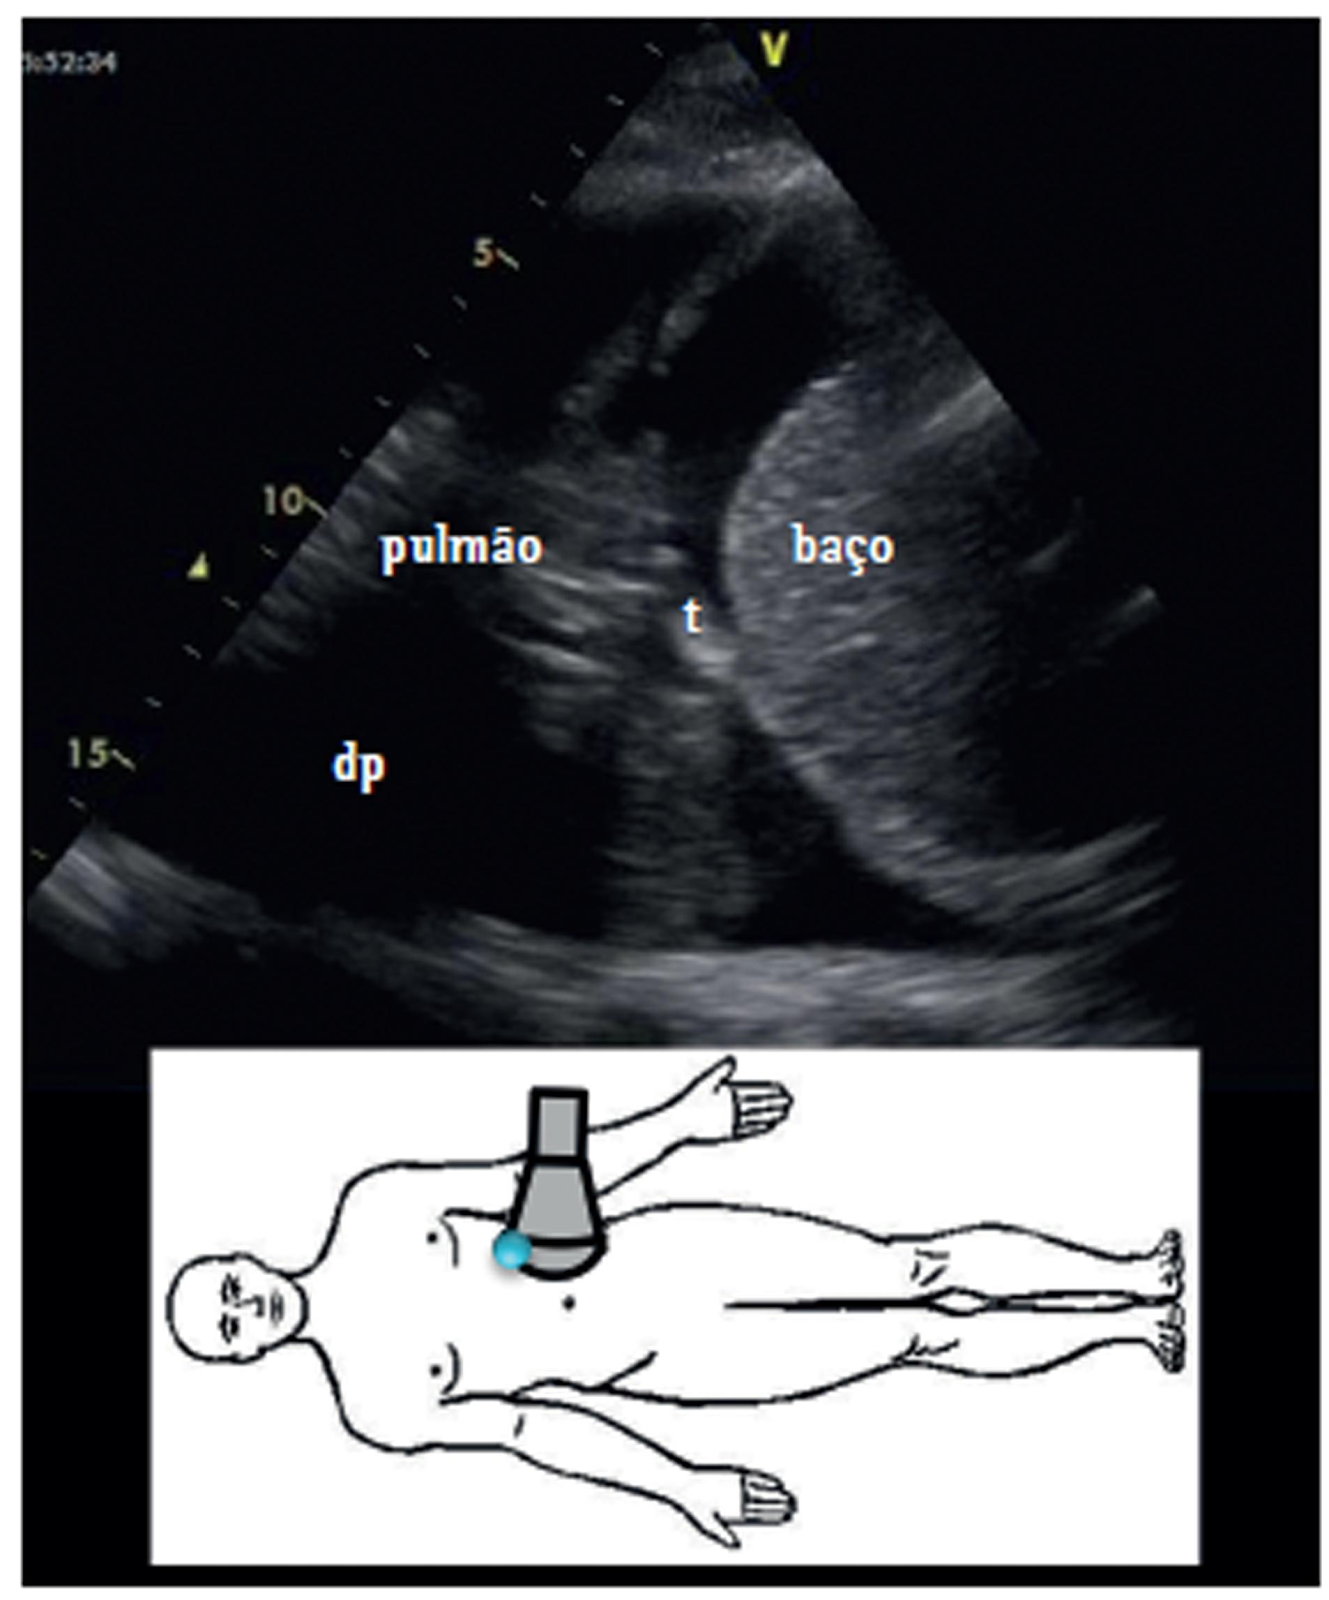

Todo paciente com suspeita de derrame pleural deve ser submetido a um exame de imagem do tórax para diagnosticar a sua extensão. A ultrassonografia (USG) é um exame melhor que a radiografia de tórax em decúbito lateral (incidência de Lawrell) para avaliação da suspeita do problema, e muito útil como guia para a toracocentese.

Na incidência de Lawrell, o paciente é posicionado em decúbito lateral no hemitórax acometido, sendo essa a incidência mais sensível para visualizar o derrame. Nesse caso, observa-se a lâmina de líquido formar uma linha no hemitórax, e se ela apresentar pelo menos 10mm (1cm), há pelo menos 200 a 300 mL de líquido no espaço pleural, a toracocentese diagnóstica está autorizada.